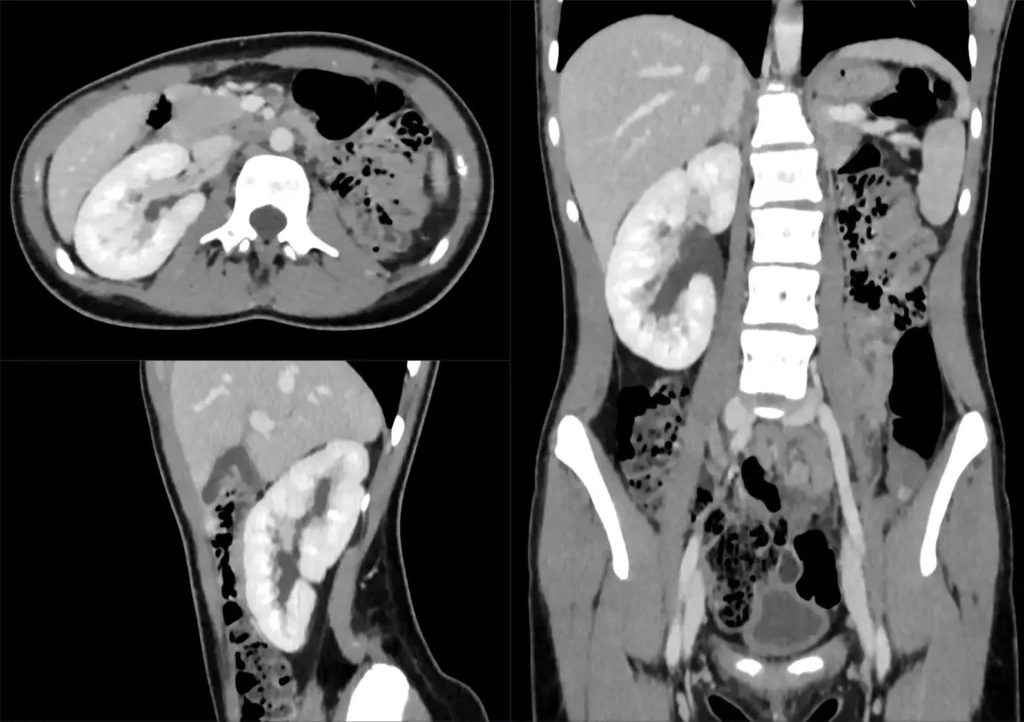

Die Geburt mit nur einer Niere, auch bekannt als einseitige Nierenagenesie, ist eine relativ häufige Erkrankung. Etwa 1 von 1000 Menschen wird mit nur einer Niere geboren. In den meisten Fällen ist die fehlende Niere nicht durch eine Krankheit oder eine genetische Störung entstanden, sondern einfach nicht ausgebildet. Diese Menschen leben in der Regel ein völlig normales Leben, ohne dass ihre Gesundheit beeinträchtigt wird. Es gibt jedoch einige wichtige Dinge, die sie beachten sollten, um ihre Gesundheit zu erhalten.

Menschen mit nur einer Niere haben eine geringere Filterkapazität, da die verbleibende Niere die Arbeit der fehlenden Niere übernehmen muss. In den meisten Fällen kompensiert die verbleibende Niere die fehlende Funktion gut und ermöglicht ein normales Leben. Es ist jedoch wichtig, die verbleibende Niere zu schützen, um eine Überlastung zu vermeiden.